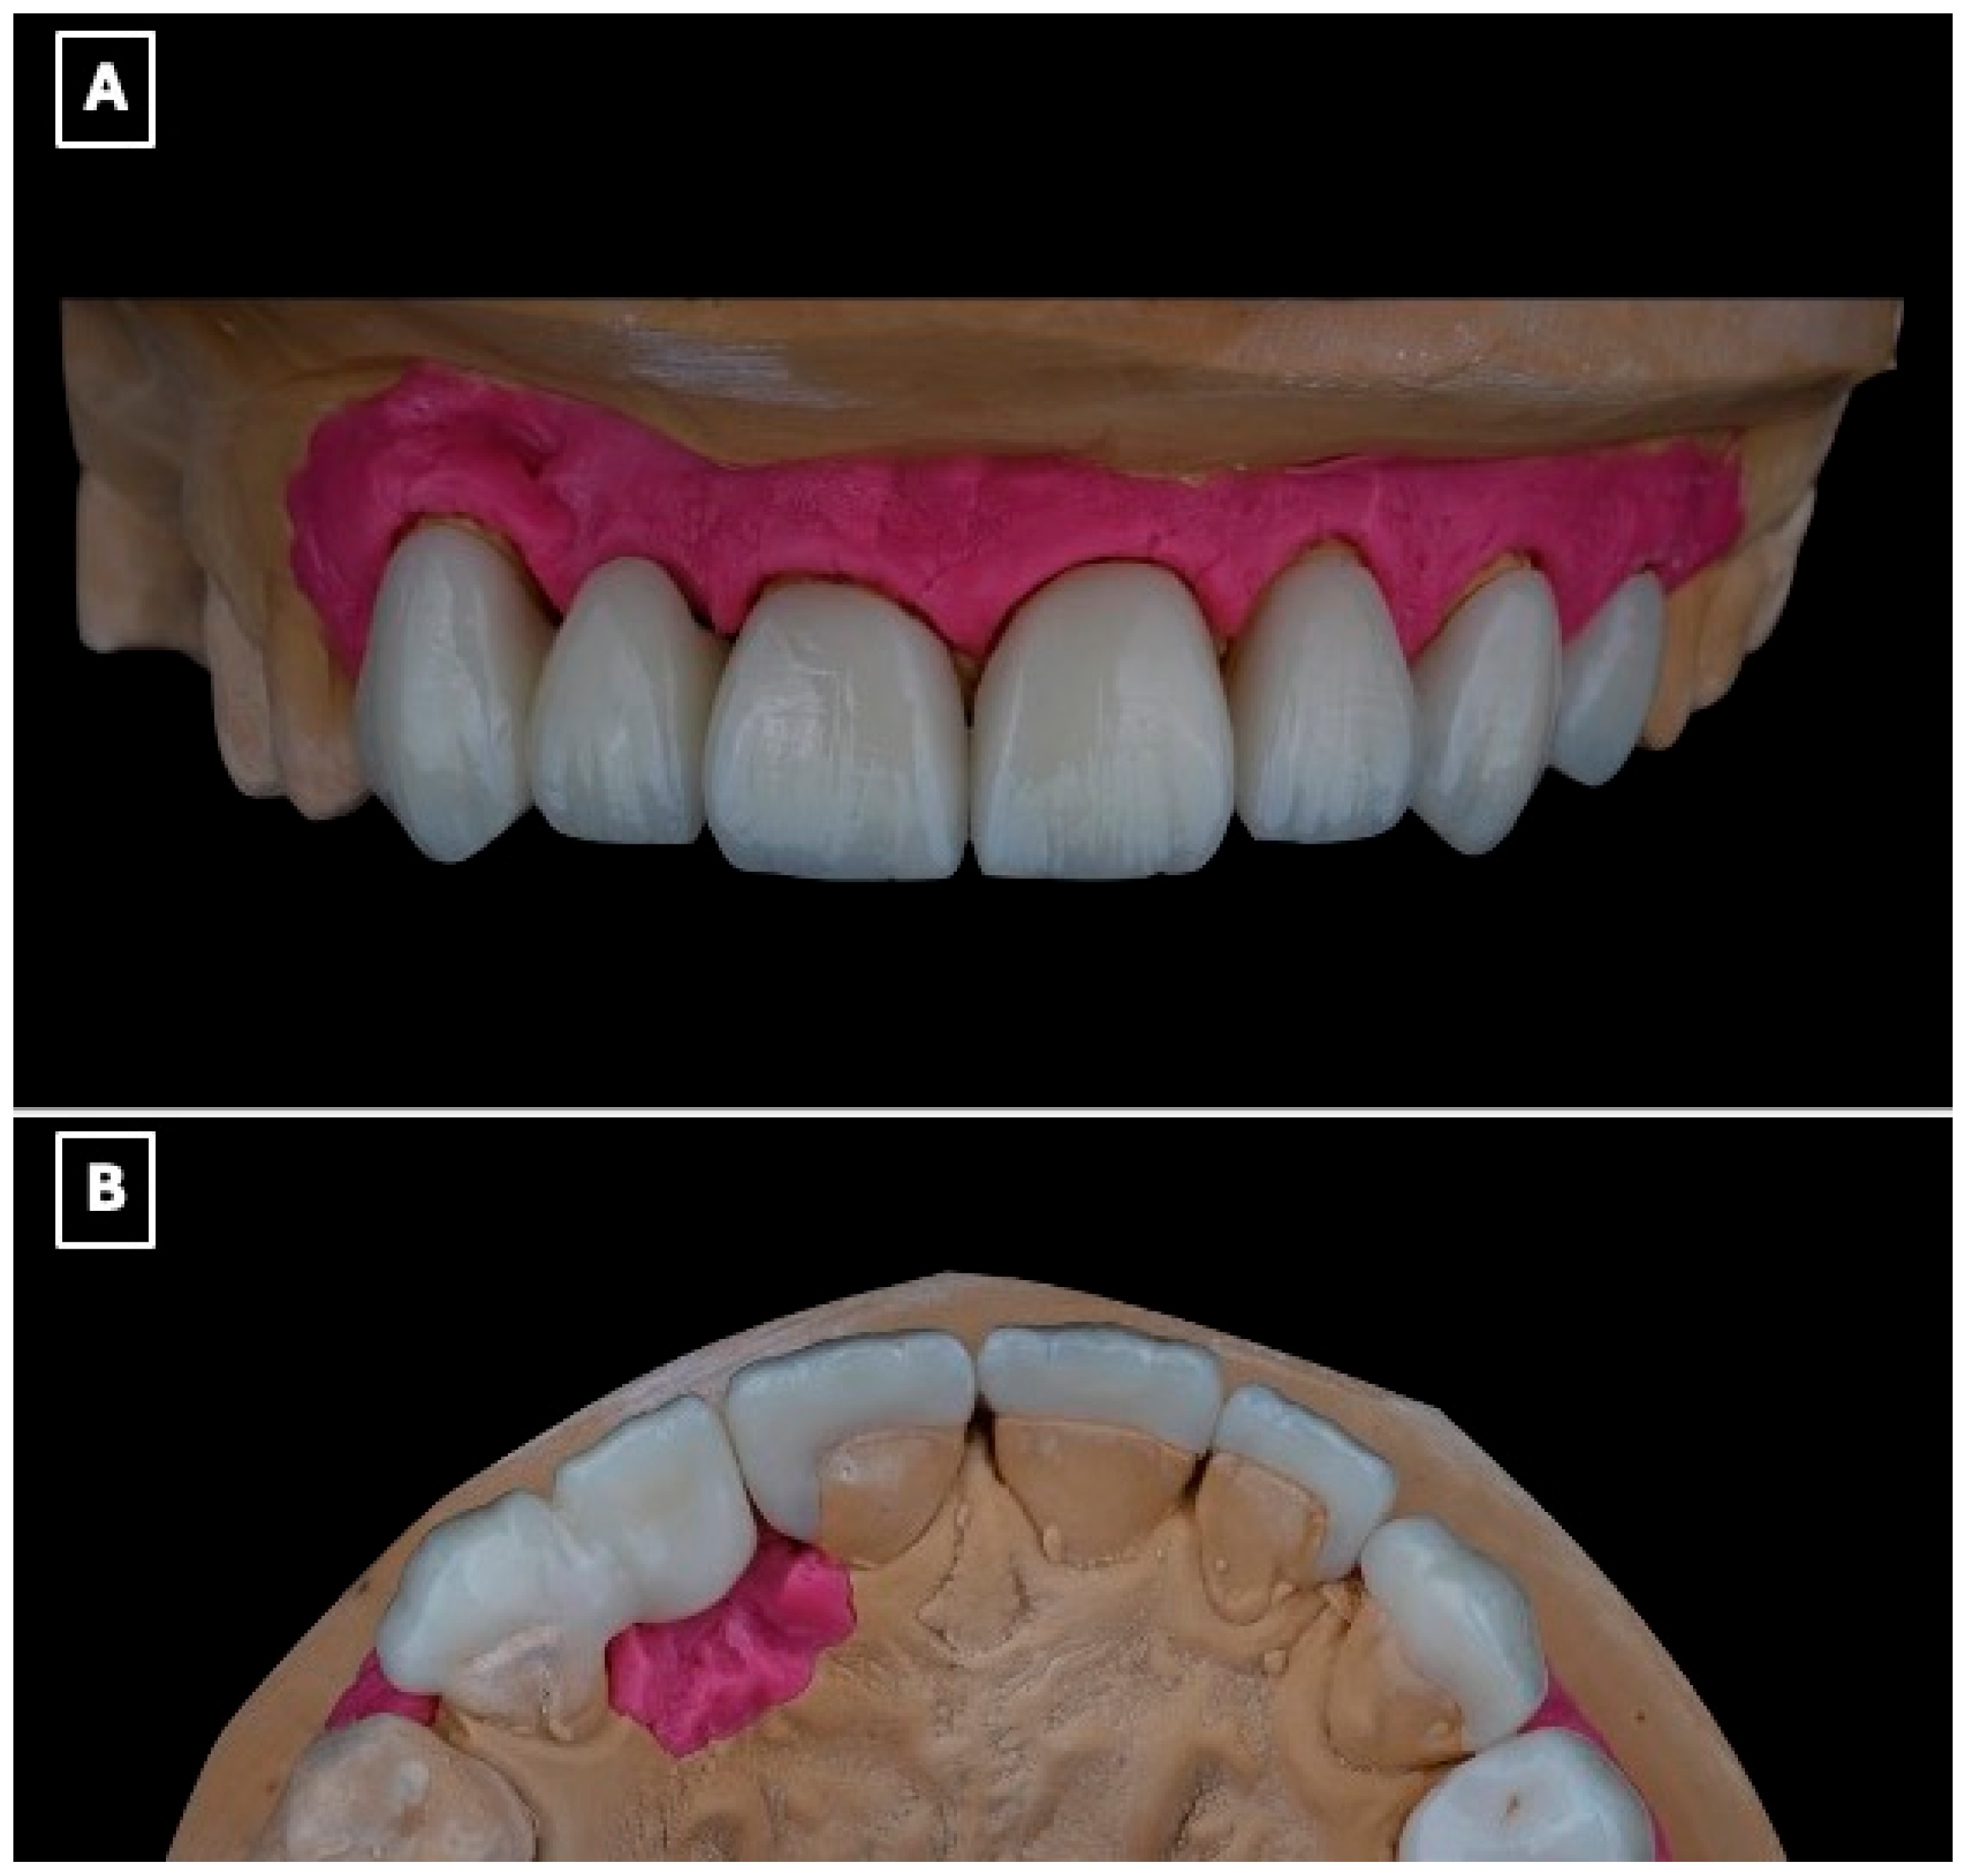

Before adhesive cementation, the intaglio surface of the lithium disilicate restoration was treated to enhance micromechanical and chemical retention. The bonding surface was conditioned with 5% hydrofluoric acid (IPS Ceramic Etching Gel, Ivoclar Vivadent, Schaan, Liechtenstein) for 20 s, followed by thorough rinsing and air drying. Subsequently, a silane coupling agent (Monobond Plus, Ivoclar Vivadent, Schaan, Liechtenstein) was applied to facilitate chemical interaction between the ceramic substrate and the resin cement (Figure 5A,B).

Figure 5.

Surface conditioning protocol of the lithium disilicate single-retainer cantilever resin-bonded fixed dental prosthesis prior to adhesive cementation. (A) Intaglio surface of the prosthesis before surface treatment, illustrating the defined bonding surface of the enamel-retained cantilever retainer and pontic, which is critical for maximizing adhesive surface area and stress distribution. (B) Sequential surface conditioning procedures, including hydrofluoric acid etching to selectively dissolve the glassy matrix and create micromechanical surface roughness, followed by application of a silane coupling agent to promote chemical bonding between the lithium disilicate ceramic and the resin cement, thereby enhancing bond durability and long-term retention in cantilever resin-bonded designs.

The enamel surface of the abutment tooth was selectively conditioned using 37% phosphoric acid gel (Total Etch, Ivoclar Vivadent, Schaan, Liechtenstein), followed by rinsing and controlled air-drying to maintain an enamel-restricted bonding substrate. A universal adhesive system (Adhese Universal, Ivoclar Vivadent, Schaan, Liechtenstein) was then applied according to the manufacturer’s recommendations. Cementation of the resin-bonded fixed dental prosthesis was performed using a light-cured resin cement (Variolink Esthetic LC, Ivoclar Vivadent, Schaan, Liechtenstein), with polymerization from multiple orientations to ensure adequate curing at the enamel-ceramic interface (Figure 6A–C). Excess cement was removed during the elastic phase, and occlusal refinement was subsequently carried out to eliminate static, functional, and excursive contacts on the pontic and retainer, thereby limiting mechanical loading on the cantilever restoration (Figure 6C).

Figure 6.

Adhesive cementation of the lithium disilicate single-retainer cantilever resin-bonded fixed dental prosthesis using a light-cured resin cement. (A) Intraoral try-in and seating of the prosthesis prior to polymerization, confirming complete seating of the cantilever retainer, passive adaptation at the adhesive interface, and absence of premature contacts that could induce tensile or shear stresses. (B) Removal of excess resin cement during the gel phase following initial light activation, a critical step to prevent marginal overhangs, reduce plaque retention, and minimize the risk of gingival inflammation or marginal discoloration at the enamel-ceramic interface. (C) Final intraoral view after complete polymerization, demonstrating stable marginal adaptation, controlled occlusal scheme with elimination of functional contacts on the pontic, and harmonious esthetic integration of the restoration within the anterior smile zone, which are essential factors for long-term clinical success of cantilever resin-bonded prostheses.

The final restoration demonstrated harmonious integration with the adjacent dentition, with appropriate tooth proportions, shade matching, and alignment within the anterior smile zone (Figure 7).

Figure 7.

Postoperative intraoral view demonstrating the final lithium disilicate resin-bonded fixed dental prosthesis and laminate veneers. The image illustrates harmonious integration of the cantilever RBFDP within the anterior dentition, with appropriate tooth proportions, shade matching, and surface texture continuity relative to the adjacent natural teeth and veneers. The restoration exhibits favorable soft-tissue adaptation, stable gingival margins, and a natural emergence profile of the pontic, supporting both esthetic outcomes and periodontal health. Occlusal harmony in the anterior region is maintained, with no visible functional loading on the pontic, consistent with biomechanical principles for long-term success of single-retainer cantilever resin-bonded prostheses.

2.5. Follow-Up

The patient reported satisfaction with the esthetic and functional outcomes of the treatment. Follow-up evaluations at 1 week, 1 month, 6 months, 1 year, and 18 months showed maintained adhesive retention, healthy peri-abutment soft tissues, and no evidence of technical or biological complications during the observation period (Figure 8A–C).

Figure 8.

Intraoral views at the 18-month follow-up demonstrate clinical stability of the restoration. (A) Frontal intraoral view showing stable esthetic integration of the cantilever RBFDP and laminate veneers within the smile. (B) Close-up frontal view highlighting maintained color stability, intact adhesive margins, and healthy peri-gingival tissues, suggesting favorable short- to medium-term adhesive performance. (C) Lateral intraoral view illustrating functional integration and preservation of occlusal relationships, with no evidence of chipping, debonding, or excessive wear at the cantilever region.